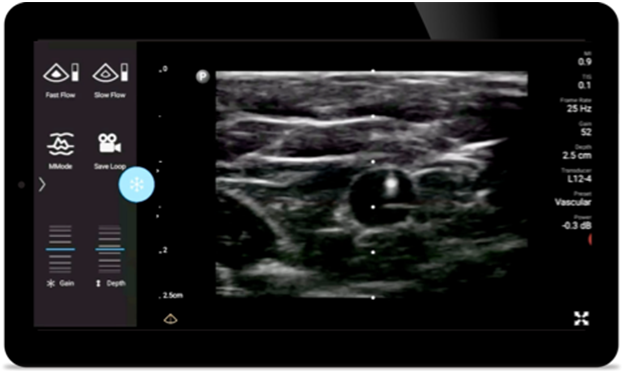

Verminder complicaties tijdens naaldgeleide procedures

De Lumify draagbare echografieoplossing voor loco regionale anesthesiologie helpt u bij het visualiseren van de omliggende zenuwen, vaten, omliggende weefsels en naald-in situ tijdens de procedure.

Verminder complicaties